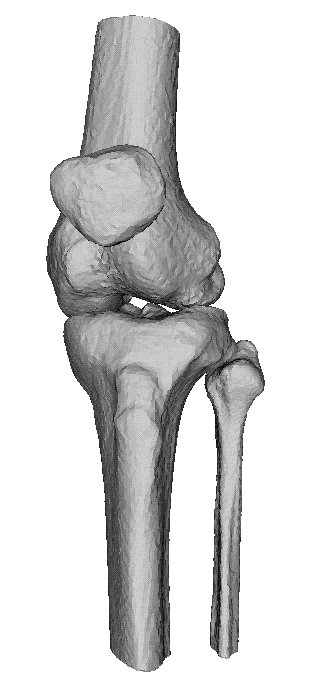

Dankzij de moderne computertechnieken is het niet allen mogelijk om

axiale beelden te maken. (lees schijfjes dwars op het lichaam) Maar ook

om die beelden te reconstrueren tot een 3D-model. Dit geeft vaak een

duidelijk beeld van het bot, en zijn letsel.